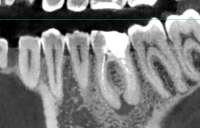

>>1326884 (OP) сап медач, удалили зуб мудрости (точь-в-точь было как на пике, только он еще торчал малость). Прошла неделя. Ноет пара соседних зубов. Еще один зуб стал гиперчувствителен к холоду (при промывании ноет пока отвар не нагреется щекой). Хирург говорит подождать, скорее всего нерв задели при удалении так как удаление сложно. Это возможно? Говорит если в течении трех недель не пройдет будут с терапевтом смотреть че у меня. До этого на зубы эти не жаловался. Может стоит самому сходить и сделать КТ челюсти чтобы узнать что у меня там?